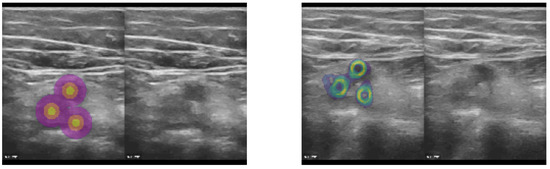

2.1.3. Sparse Supervision

As mentioned before, our proposed approach excels when limited and sparse ground truth annotations are available for training. We rely on only a few (1–5) 2D landmarks in each frame of our training database. To enable the use of landmark supervision as drop-in replacement for spatial transformer loss functions, which rely on applying the full estimated deformation to a (multi-channel) label image, we created three concentric rings with increasing label number around each annotated 2D position (see example image in Figure 3) yielding three-class heatmaps around the manual landmarks. Subsequently, a standard soft Dice loss could be employed and the use of affine augmentation during training became easier. To improve the coverage of the estimated transform, and avoid overfitting of the features towards specific target anatomies that were annotated in the training dataset, we added the unsupervised MIND loss [24] with the following extension. Instead of using only 8 immediate neighbours to compute local contrast-invariant self-similarities, we sampled 64 2D offsets for patch comparisons that provided a better context representation. Finally, a loss on the standard deviation of the Jacobian determinant of the estimated displacements was used, motivated by the fact that this metric was used in Learn2Reg [7] as a quantitative smoothness measure.

Figure 3. The concept was to employ sparse landmarks as spatial transformer (warping) loss by generating pseudo segmentation labels that could be directly used in affine augmentation and Dice loss functions. Based on either segmentation centroids or manual landmark coordinates (here vessel centres), we generated three concentric circles (heatmap labels) that defined the precise location, as well as a robust neighourhood of each landmark, for improved supervision. Left: Heatmap labels, along with original CoCoAI frame. Right: Tenth temporal frame in sequence with overlay of all warped heatmaps (middle label) averaged. It can be seen that the motion was very well compensated and only minimal deviations of the warped labels from their ground truth locations was visible.